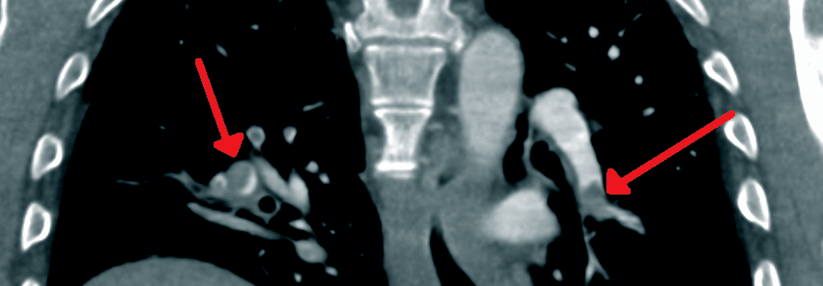

Ein 30-jähriger Patient mit massiver Adipositas wurde wegen starker Dyspnoe ins Krankenhaus eingewiesen. Die Spiral-CT zeigte eine Pulmonalembolie im linken Unterlappen und eine Pneumonie. Vor fünf Monaten hatte er schon einmal eine bilaterale Lungenembolie gehabt, berichtete Prof. Dr. Alexander Rosenkranz von der Nephrologie an der Universitätsklinik Graz, stellvertretend für Prof. Dr. Sabine Schmaldienst, Klinik Favoriten Wien. Damals war eine orale Antikoagulation mit einem Vitamin-K-Antagonisten für sechs Monate angesetzt worden. In der Familienanamnese fiel auf, dass der Vater des Patienten an einer Lungenembolie verstorben war.